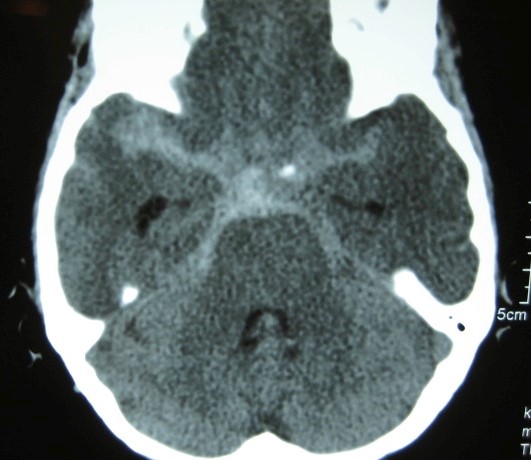

下記[図表1]のCT画像のように、検査をすれば診断は一瞬にして可能なのです。